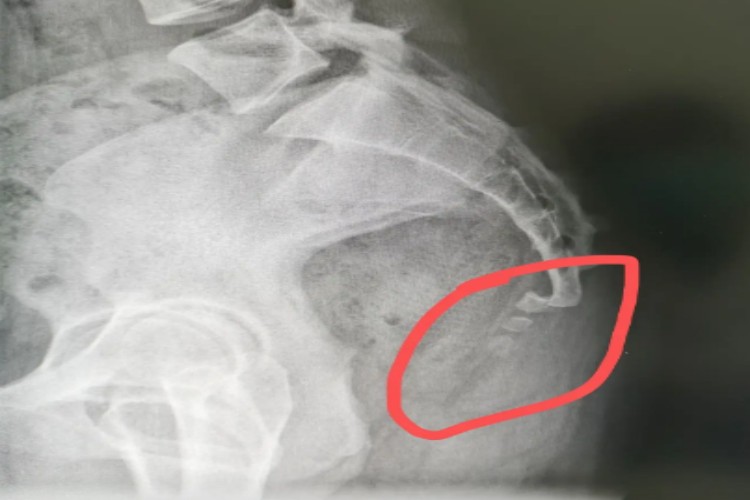

由于尾骨的生理位置和结构特点,如不慎跌倒,臀部着地,尾骨尖直接撞击于坚硬的物体,可致使尾骨骨折或者脱位,并由于肛提肌和尾骨肌的牵拉作用,使骨折端向前方或是侧方移位。

发生尾骨骨折后患者会在坐位、站位或者行走、跨台阶时疼痛加重,伴肛门坠胀感、里急后重等症状。症状轻者可卧床1-2周,坐位时使用气垫保护,一般可自行恢复。病情严重者需手术进行复位治疗。